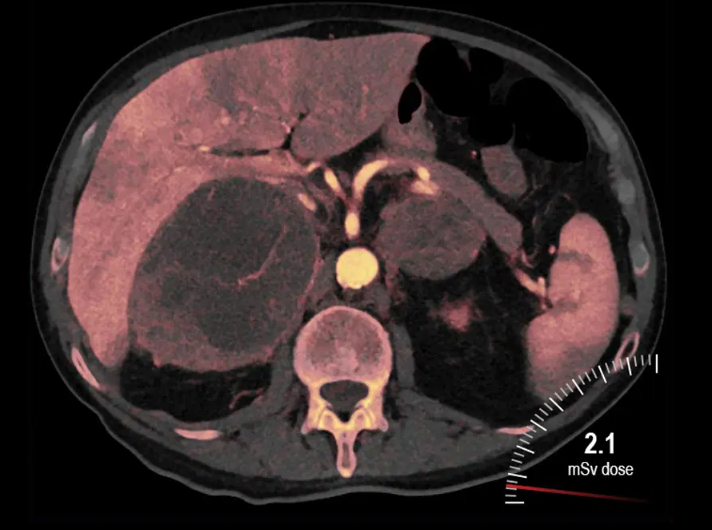

- Oncologia: realce tumoral com contraste de iodo;

A Dual Energy CT oferece vantagens como menor necessidade de contraste iodado, imagens com melhor relação sinal/ruído e análise mais precisa de tecidos moles. Além disso, permite reconstruções com realce seletivo e geração de imagens virtuais sem osso ou sem contraste.